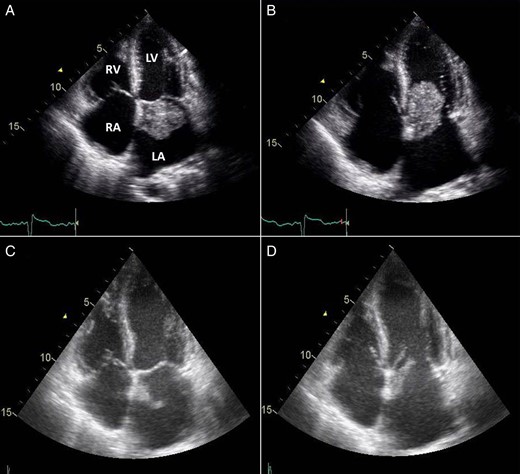

Transthoracic echocardiogram (TTE) revealed a 4.8 × 2.5 cm mobile mass arising from the interatrial septum of a severely dilated left atrium, causing moderate left ventricular inflow obstruction with a mean gradient of 12 mmHg and trace mitral regurgitation (Fig. 1A and B). There was severe tricuspid regurgitation with a systolic pulmonary artery pressure of 61 mmHg. The patient described symptoms of angina before her current hospitalization for shortness of breath. For that reason, a coronary angiogram was ordered before her surgery and revealed 80% lesions in the mid-left anterior descending artery and a 70% stenosis at the origin of the posterior descending artery of a dominant left circumflex artery.

TTE 4-chamber view during systole (A) and diastole (B) showing a large LAM attached to the interatrial septum and obstructing diastolic filling of the left ventricle and follow-up four-chamber view during systole (C) and diastole (D) showing a marked reduction in the size of the LAM (LA, left atrium; LV, left ventricle; RA, right atrium; RV, right ventricle).

The next morning after her coronary angiogram, the patient suddenly showed signs of confusion and began to experience slurred speech and left-sided facial droop with left-sided hemiplegia. She was intubated to protect the airway and was sent for an urgent computed tomography (CT) scan of the head, which revealed a hyperdense minute clot lodged at the right internal carotid artery bifurcation. Accordingly, tissue plasminogen activator thrombolytic therapy was initiated. A repeat TTE showed that the mass was markedly decreased in size (2.1 × 0.9 cm) compared with a previous study, likely due to embolization (Fig. 1C and D).